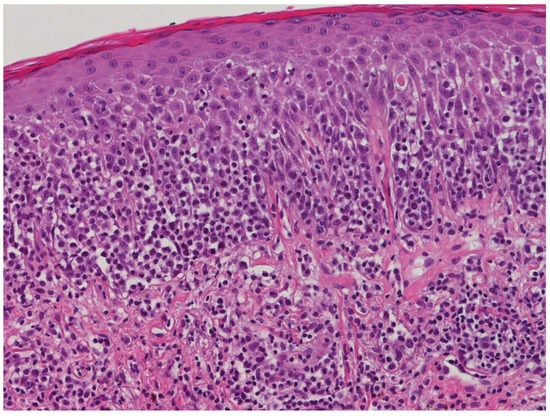

2. Case Presentation